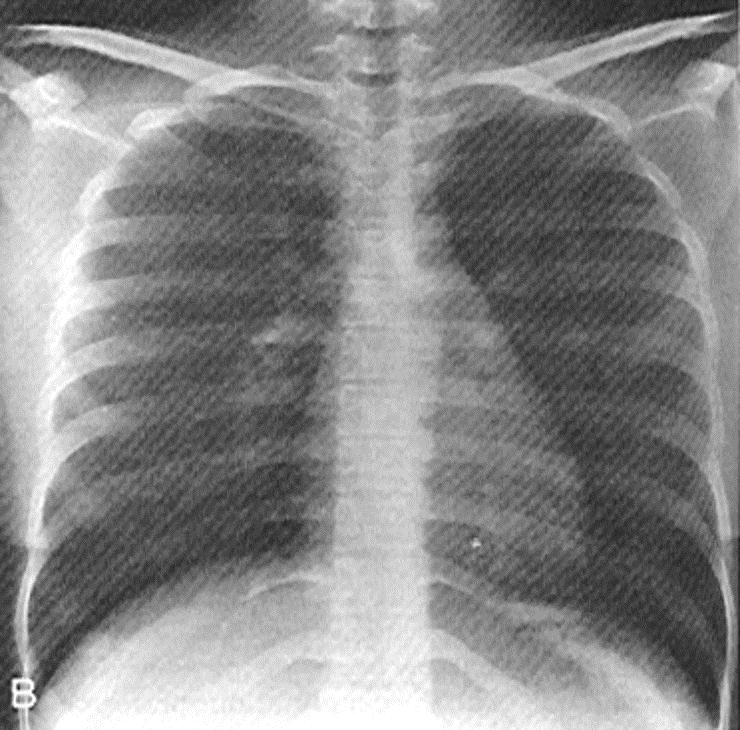

what view is this?

three indentifiers

how far is the xray source from the plate in an AP? PA? Lateral?

AP is 3 feet

why is an AP view usually taken supine

they are taken on the portable when the patient cant make it to radiology